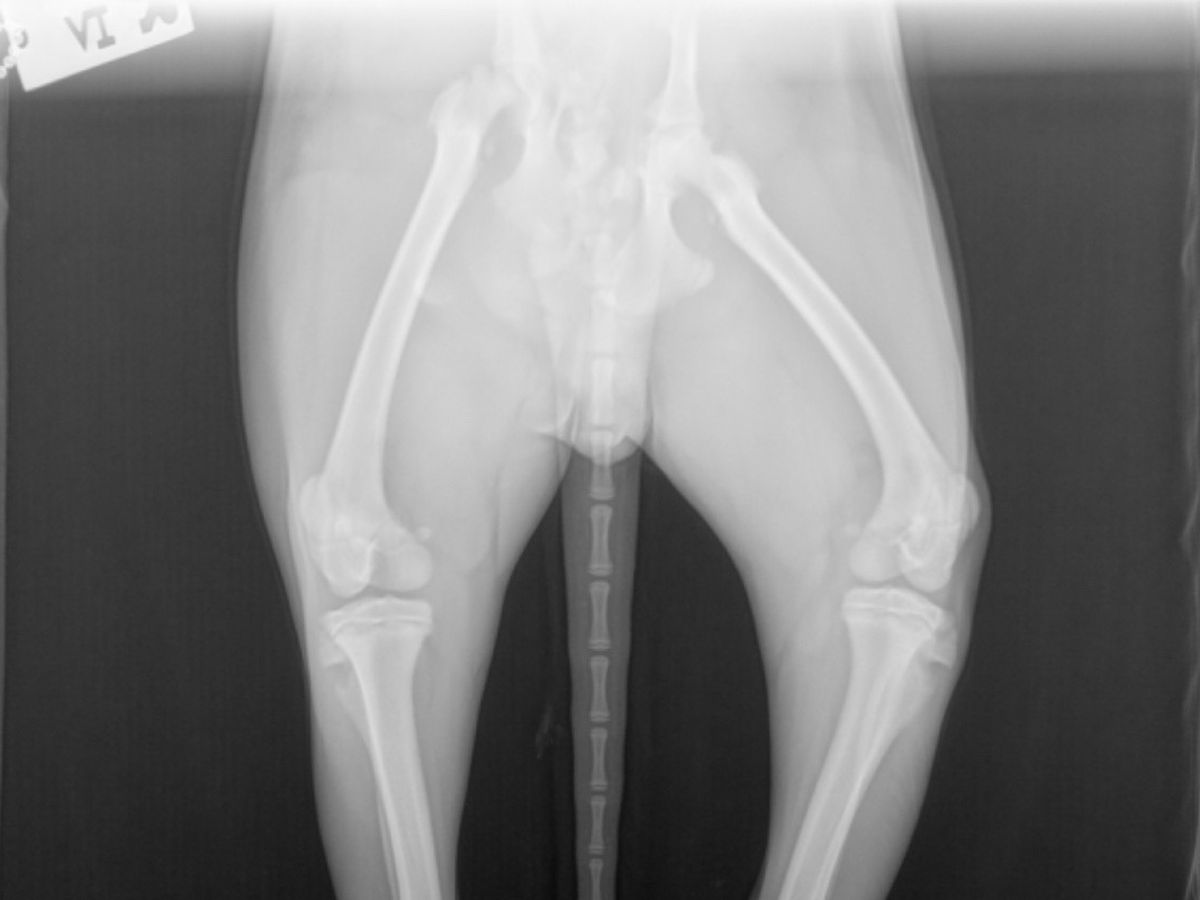

Pelvic Sugery for Zeus

My name is Sandra and I’m raising money for my 8 month old puppy Zeus. Zeus was ran over by a truck on Wednesday and cannot walk. I took him to the vet and they told me that his pelvic bone is detached which is why he can’t get up or walk. I’ve spent over $600 on him and I just can’t afford to pay anymore. Zeus is in a lot of pain and medication isn’t really doing much. I love him and I hate seeing him suffer. Please help me raise money for his surgery that will be held at Wilcox Veterinary. Anything helps. Thank you!!